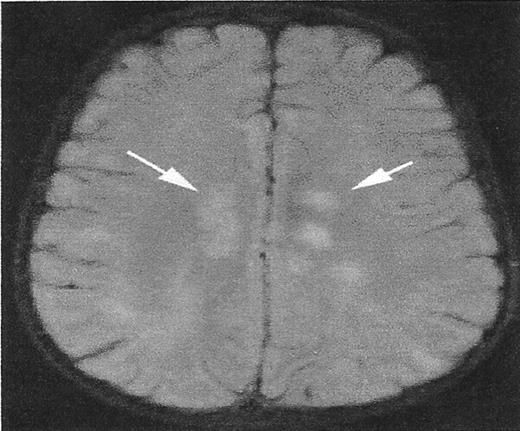

MRI mimics of silent cerebral infarcts

While the definition of the infarct-like lesion has been established, there are MRI signal abnormalities that mimic SCI but have distinct etiologies. Figure 1 illustrates this point. The T2 signal hyperintensities noted in the deep white matter are the result of acute disseminated encephalomyelitis, rather than SCA. However, the clinical setting would help distinguish these two entities. Other mimicry includes the sequelae of periventricular leukomalacia, dilated perivascular spaces, and delayed myelination in the terminal zones.

A lesion that mimics silent cerebral infarct (SCI).

High signal intensity lesions in the central white matter of both cerebral hemispheres (white arrows) in a child with acute disseminated encephalomyelitis. SCI often have a similar appearance.